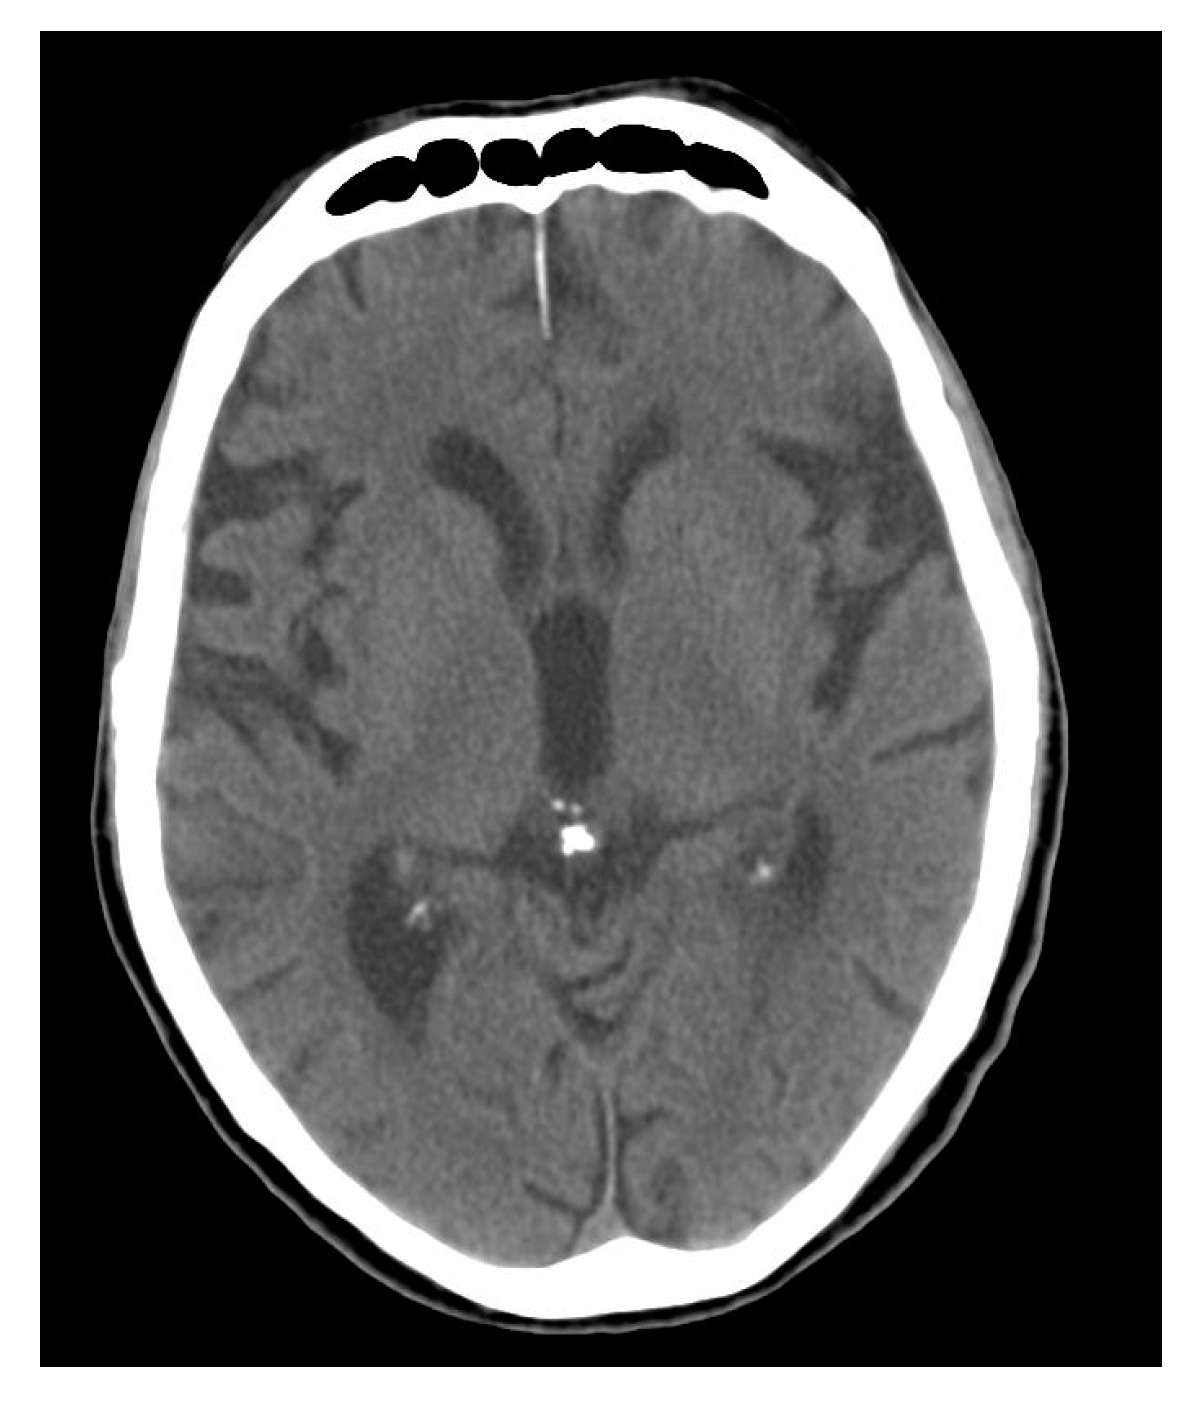

Calcium accumulates in the pineal gland in the apatite structure, similar to that found in bones and teeth [63,85,86], and as calcium carbonate (calcite) [87]. The process is initiated in childhood [88], and even in newborns [89,90], so some scientists see it as a physiological phenomenon [64]. It is, however, difficult to agree with such a conviction in the face of ample evidence showing the relationship between pineal calcification and various pathological states. This includes mental illnesses and disorders [91,92,93], neurodegenerative disorders [94,95], primary brain tumors [96], ischemic stroke [97], migraine [98], and sleep disorders [99]. The accumulation of calcium in the pineal gland is also related to aging processes [100] (Figure 4).

Figure 4.

Computer tomography (CT) scan through the brain with calcification of the pineal gland (case courtesy of Radswiki, Radiopaedia.org, rID: 11770).